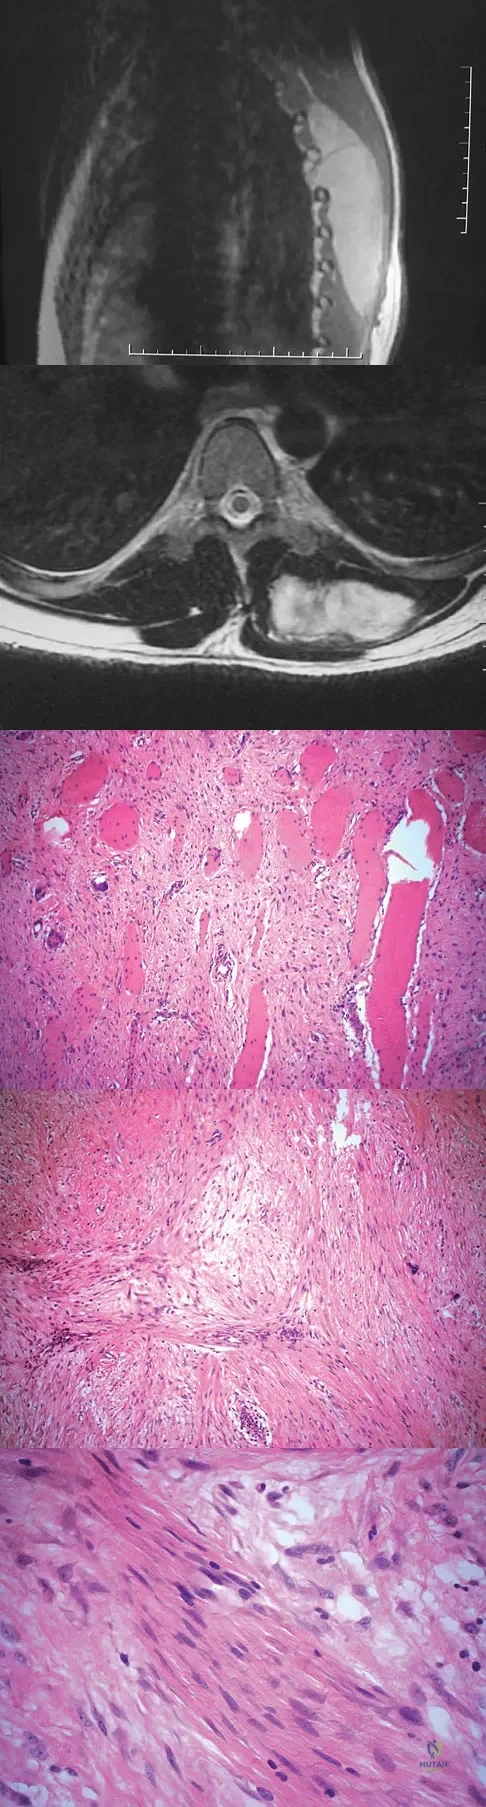

A 38-year-old man has an enlarging left paraspinal soft-tissue mass. Based on the MRI scans and biopsy specimens shown in Figures 32a through 32e, what is the most likely diagnosis?

Explanation